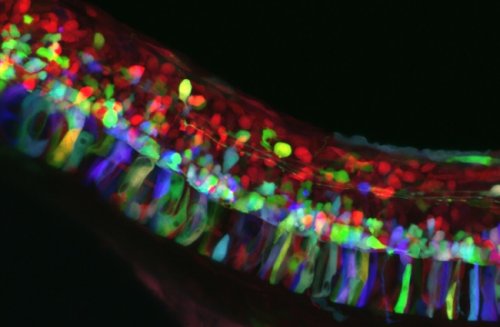

Мозговое вещество трансгенной мыши в 3D